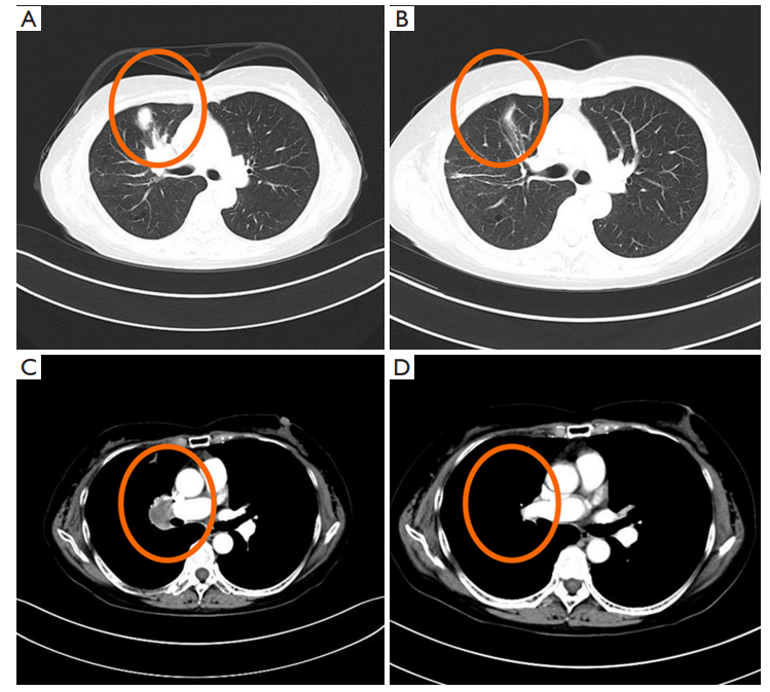

第一代 EGFR-TKI 吉非替尼治疗期间的胸部 CT 图像。(AC)在开始使用 EGFR-TKI 之前的心肺 CT 检查结果。(BD)开始使用吉非替尼后的心肺 CT 检查结果。红色圆圈代表肺部肿瘤病灶。